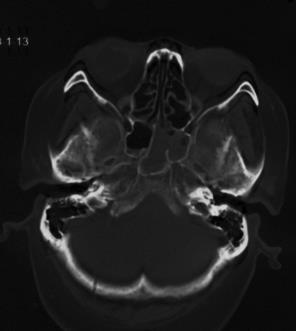

复阅2020年4月29日CT片:左侧额颞部颅骨修补、脑积水分流术后改变,人工颅板在位,双侧额颞叶、左侧枕叶及右侧小脑半球见片状低密度阴影,左侧脑室较右侧稍扩大,内见引流管在位。提示左侧额颞部颅骨修补、脑积水分流术后,双侧额颞叶、左侧枕叶及右侧小脑半球软化灶形成。

图13-15,2020年4月29日 CT片,左侧额颞部颅骨修补、脑积水分流术后,双侧额颞叶、左侧枕叶及右侧小脑半球软化灶形成。